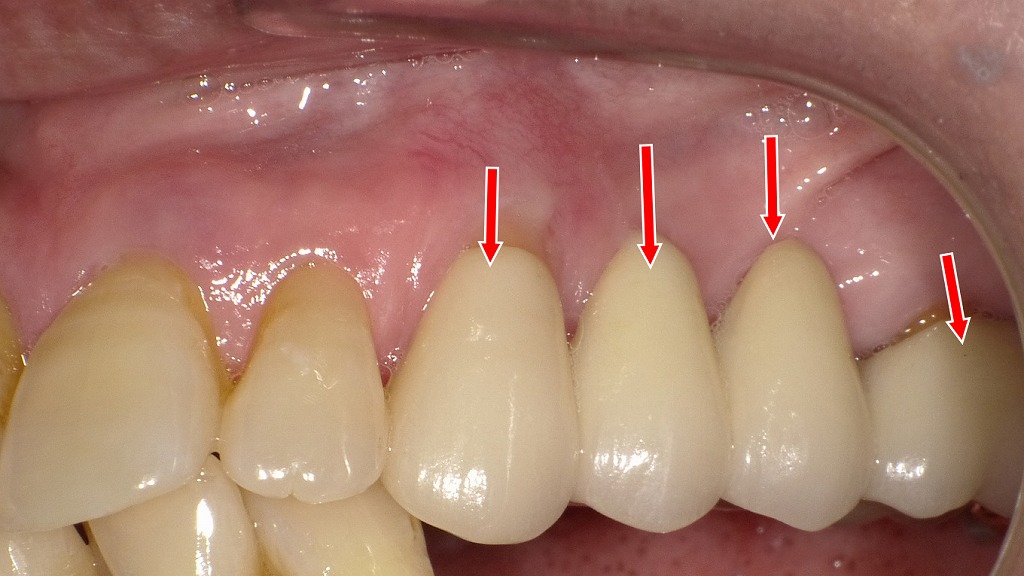

📸 フィステルによる変色・歯並びの改善例

▶ 症例3:膿の排出(フィステル)と歯の変色を改善

歯茎に**フィステル(膿の通り道)**ができたことで、歯が茶色に変色し、審美性が大きく損なわれていた症例です。

術前(症例3)

赤い矢印の場所にフィステルが出来ています。そして歯が茶色に変色しています。

根管内が細菌感染をして膿がフィステルから出ています。

術後(症例3)

根管治療を行ってフィステルが消失しています。次にオールセラミックで治療したことで歯並びもやや改善出来ています。

治療内容:

- 根管治療で感染を除去 → フィステル消失

- ファイバーコアを設置し、オールセラミッククラウンを装着

結果:

変色が完全に解消されただけでなく、歯並びもわずかに整えられたことで、より自然な仕上がりに。健康面・見た目ともに満足度の高い治療となりました。